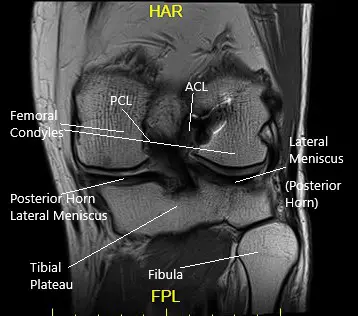

The ACL runs from the front and middle of the tibia to the outer and backward side of the femur. The ligament provides stability mainly in the front and back of the knee. The ligament also stabilizes the rotatory movement of the knee.

Posterior Cruciate Ligament (PCL)

The PCL is present behind the knee joint. Along with ACL, it provides stability in the front and back of the knee. Similar to ACL, the PCL also provides rotational stability.

The ligaments of the knee along with the meniscus provide stability to the knee. Tears or rupture of the ligaments and menisci are the most common cause of knee buckling.